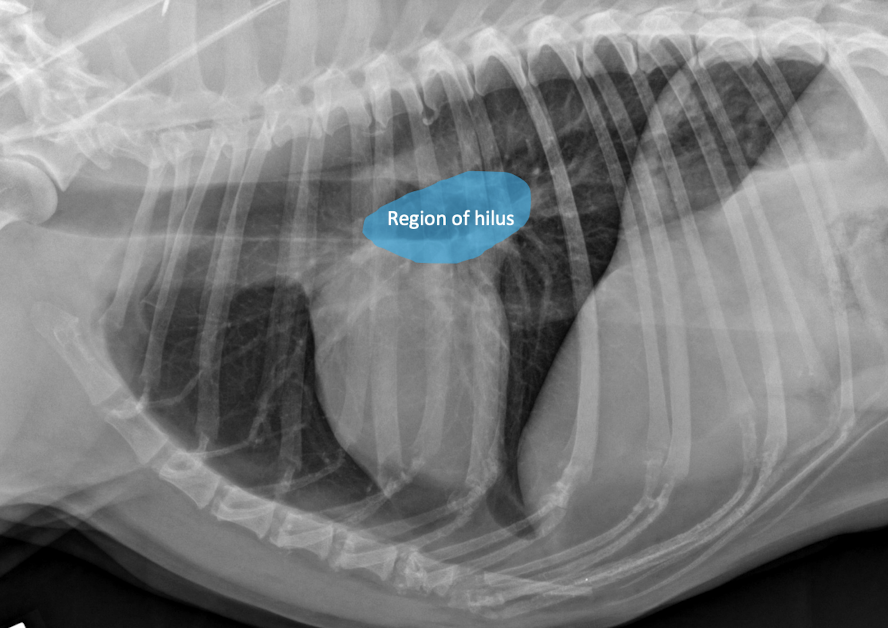

Lung Pattern? Where is the hilus?

Normal lungs